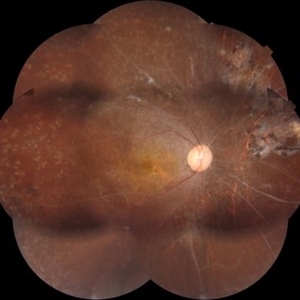

Fundus photograph (montage photography) of a 57-year-old woman with proliferative diabetic retinopathy in her both eyes.

Photographer: Nanda Lessi Hafni Eka Putri, MD (Ophthalmologist) & Ryan Mishbahuddin (Nurse), Ciawi General Hospital (Rumah Sakit Umum Daerah Ciawi)

Imaging device: DRI OCT Triton Plus

Condition/keywords: fundus photograph, montage, optical coherence tomography (OCT), swept source, wide angle imaging